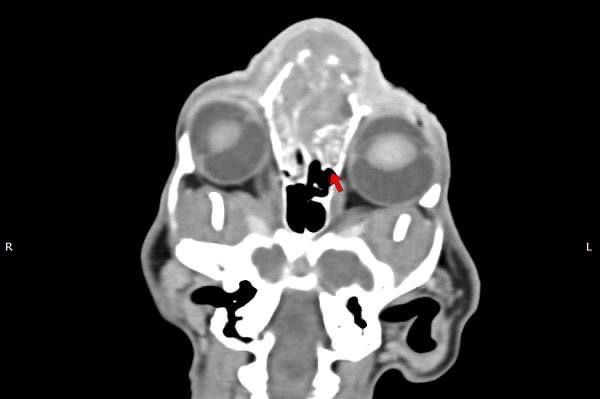

貓咪 鼻腔腫瘤腺癌 Adenocarcinoma

鼻腔腫瘤的診斷需要仰賴電腦斷層掃瞄定位病灶處,同時使用鼻腔內視鏡探查、採樣才能確診,同時有這兩項設備的醫院並不多,所以臨床事並不是那麼容易確診。

貓咪幾個月前開始打噴嚏、流鼻、鼻塞越來越嚴重,他院住院治療改善不佳後轉診至築心檢查。